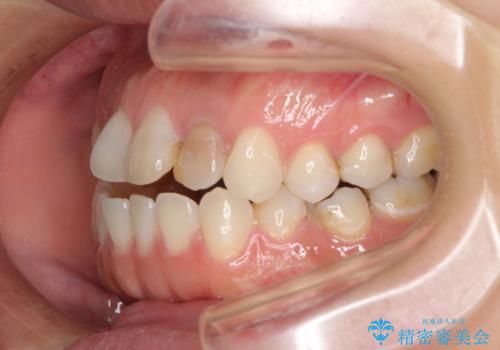

開咬と変色した前歯 インビザライン矯正とオールセラミッククラウン治療

- 前歯の開咬と失活により変色した前歯を気にして来院された患者様です。

開咬の治療は、前歯を閉じるように引っ張り出すよりも、上下臼歯を圧下(骨内にめり込ませる)させることで進める方が長期的に安定した歯列を維持できます。

インビザラインは臼歯の圧下を効果的に行えるため、インビザラインを用いて矯正治療を行うこととしました。

矯正治療が概ね終了した時点で前歯をオールセラミッククラウンにて補綴治療を行い、その後インビザラインにて細かい部分を仕上げていくことしました。